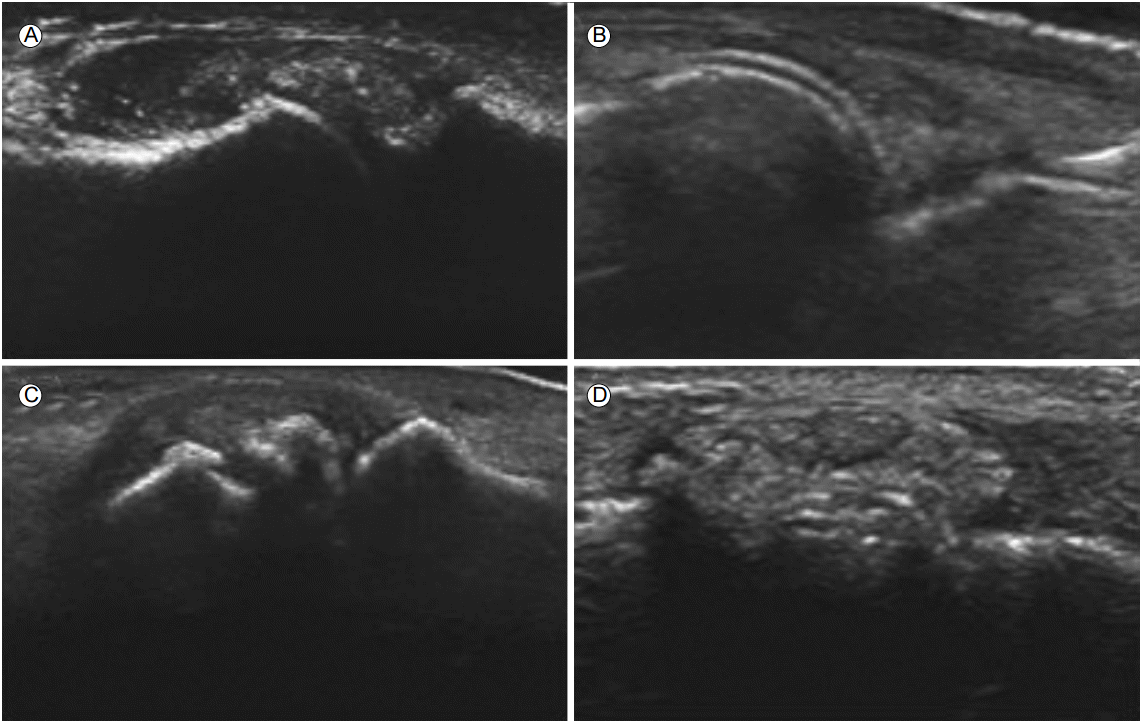

Figure 2.

Ultrasonographic findings of gouty arthritis. (A) There are hyperechoic spots in synovial tissues and synovial space making “snowstorm appearance” in first MTP joint. (B) There is hyperechoic band around the surface of hyaline cartilage of metatarsal head, named “double contour sign”. (C) There is a defect in the surface of subchondral bone margin (erosion). (D) There are circumscribed, heterogeneous aggregations with thin anechoic rim (tophi). MTP, metatarsophalangeal.

통풍관절염에서 초음파는 매우 유용하다[4,5]. 통풍에서 초음파의 적용은 다른 염증관절염처럼 침범 관절의 활막 부분이 두꺼워지고 이 부분에서의 파워도플러 신호가 확인되는 것이다[6]. 그러나 이는 대부분의 관절염에서 관찰될 수 있는 비특이적인 소견으로, 류마티스 관절염과 같은 염증성 관절염과 구분되는 점은 결정 침착이 확인되는 것인데 이는 여러 형태로 보일 수 있다. 혈중 요산 수치가 6.8 mg/dL를 초과하게 되면 혈액내 과포화 상태가 되어 체내에 녹아있던 요산이 결정화되어 생체내 모든 구조물에 침착이 가능하며, 주변 조직에 비해 초음파를 강하게 반사하기 때문에 구별이 쉽고, 탐촉자의 각도에 영향을 적게 받는다[7-9]. 1 mm 이하의 요산 결정이 고에코의 점 모양으로 보이는 것이 가장 흔하게 관찰되는 소견이다. 관절액 안에서 관찰될 경우 ‘눈보라(snow storm)’ 징후를 보이며, 활막 증식 부위 안에서 보인다(Fig. 2A). 2015년 분류 기준에도 관절 연골에 특징적인 요산 결정 침착이 포함되었다. 정상 유리질 연골은 초음파에서 고에코 음영을 띄는 두 개의 선명한 경계면으로 둘러싸여 주변 조직과 명확히 구분되는 무에코 음영 층이다[8,9]. 요산 결정은 연골의 표층면을 선호하는 경향이 있어 이 부위에 침착되면 침착 정도에 따라 국소적으로, 혹은 미만성으로 연골하 골피질에 필적하는 고에코 음영을 띄게 된다. 관절의 종단면에서 관절면을 따라 선형태의 결정 침착이 뚜렷한 두 개의 고에코 띠 형태로 보이므로 이를 이중윤곽 징후라고 한다(Fig. 2B). 이중윤곽 징후는 통풍 진단에 있어서 민감도는 43.6%로 다소 낮은 반면, 특이도는 99%로 매우 높고, 다른 관절 질환에서는 나타나지 않고 오직 통풍에서만 관찰되기 때문에 감별진단에 유용하다. 골미란은 직각의 두 탐촉면에서 모두 관찰되는 골피질 결손이며(Fig. 2C), 이환된 기간이 길고, 통풍 발작 횟수가 많거나, 통풍 결절이 동반되어 있는 질환의 경우에 더 쉽게 관찰된다. 통풍에 의한 골미란은 다른 염증 관절염과 비교하여 비대칭적으로 발생하고, 더 깊고, 파괴적인 양상을 보이며, 주위 뼈의 경화를 동반한다. 하지만 단독으로는 통풍의 진단에 특이적이지 않아, 골미란 주위의 요산 결정이나 결절의 동반 여부를 확인하여야 한다[4,7]. 결절은 세포 밖에 요산 결정이 침착하여 이물 거대세포(foreign body giant cell)와 단핵구들에 둘러싸여 육아종 유사 구조를 보이는 것으로 저에코 음영의 작고 균일한 결절로 보이거나 고에코 음영을 띄는 테두리에 둘러싸인 양상을 보이기도 한다(Fig. 2D).초음파는 무증상의 고요산혈증 환자에게서 요산강하제 치료를 결정하는데도 임상에서 유용하다[10]. 일본의 통풍 및 고요산혈증 치료 가이드라인에서도 무증상이더라도 혈청요산이 9 mg/dL 이상인 경우 요산강하 치료를 권고하는데 실제로 통풍관절염 발작이 없는 무증상의 환자에서 초음파상 제1 중족저지(metatarsophalangeal) 관절에서 활막 비후와 요산 결정을 시사하는 고에코 음영이 관찰되기도 한다. 급성 염증기에 관절강내 요산 결정은 항상 존재하는 것은 아니며 결정 침착이 없더라고 요산의 농도가 지속적으로 높으면 임상적으로 통풍관절염, 구조적 손상, 통풍 결정으로 진행될 가능성이 높아지므로 요산강하 치료를 고려한다. 모든 시기의 통풍관절염에서 항염증이나 요산강하 치료에 대한 파워도플러에서 염증 소실이나 요산 결정 감소를 초음파를 통해 확인 가능하다. 요산강하 치료는 대부분 장기간 지속되므로 임상적 관해나 재발을 평가할 때도 역시 유용하다.